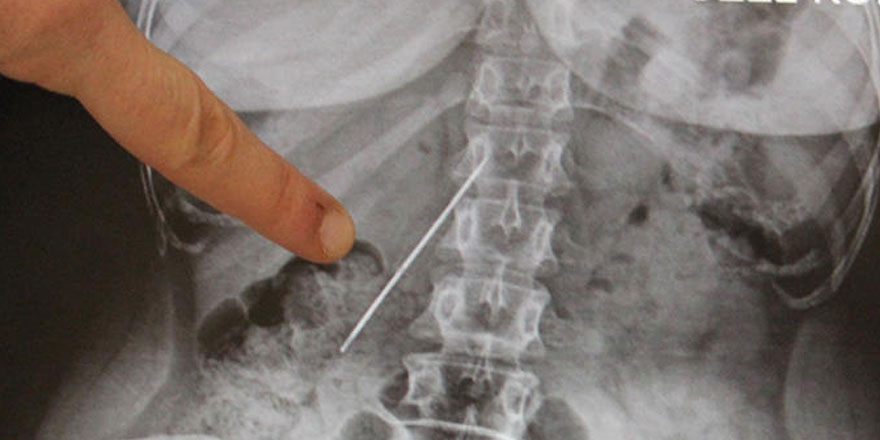

Doktorlar çekilen filmde hastanın karın bölgesinde 15 santimetre uzunluğunda bir iğne tespit etti. Bir hafta sonra ameliyata alınan Çalışkan'ın vücudundaki iğne yerinden kaydığı için çıkarılamadı. Başarısız geçen operasyonun ardından çekilen filmde, iğnenin hastanın sağ böbrek ile kalın ve ince bağırsağa yakın yerde olması nedeniyle yeni bir operasyon yapılamadı.

İğnenin zamanla hastanın yaşam kalitesini etkilediğini ifade eden Arazi, "Bu iğne çok tehlikeli bir yerdeydi. Sağ böbreğe yakın bir yerle, ince ve kalın bağırsak arasında duruyordu. Ameliyattan önce 15 santimetre uzunluğundaki iğneyi çıkarmak için bir planlama yaptık. Diğer organlara zarar vermeden bir saat süren operasyonun ardından çıkarmayı başardık." diye konuştu.